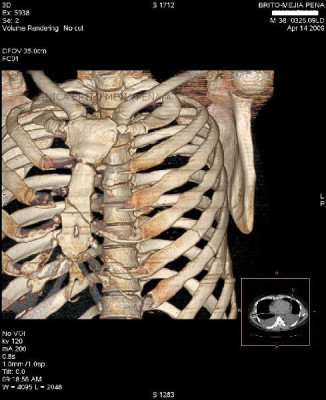

Instrumentalización columna 3D

Instrumentalización columna ósea